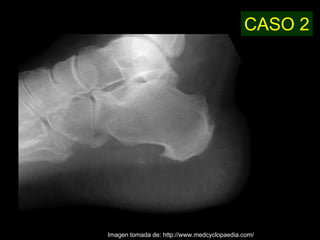

Este documento describe la acromegalia, una condición causada por un exceso de hormona de crecimiento producida por la hipófisis. Provoca un crecimiento anormal de las extremidades, la cara y los órganos internos. Sus síntomas incluyen prominencia de la mandíbula, las manos y los pies, así como engrosamiento de la piel y huesos. Generalmente se debe a un adenoma de la hipófisis y su diagnóstico se realiza mediante pruebas de sangre y resonancia magnética.